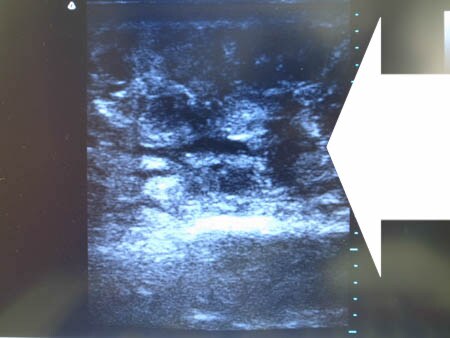

同様に左二の腕 ↓ ↓ ↓

↓ ↓ ↓

左ちからこぶ

右ちからこぶ

上の写真を見ればわかると思いますが

手術直前の皮下脂肪層はしっかりと厚みがありますが 手術直後の皮下脂肪層はほとんどありません。 確実に根こそいだ証ですね。